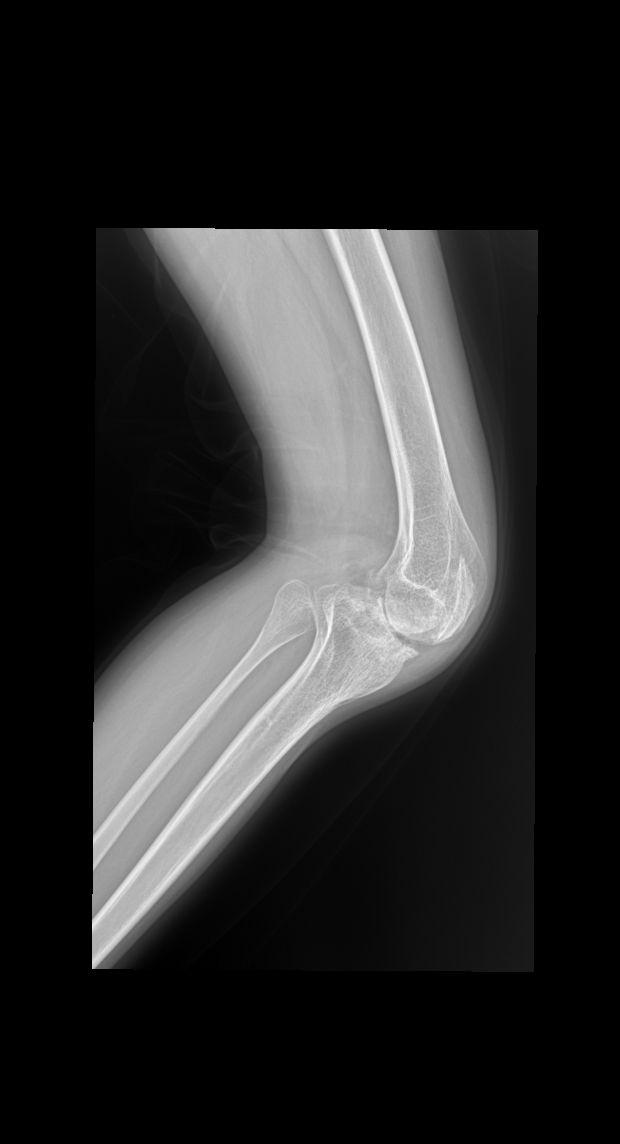

血友病